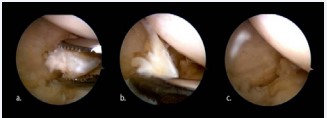

A 44 year old patient, male suffering from rheumatoid arthritis, complaining pain and clamping of the right knee for 5 years during the daily routine activities, with no associated trauma. The patient presents with a history of physiotherapy treatment and two arthroscopic procedures, with no improvement of symptoms. Radiographic examination revealed an image consistent with an intra-articular loose body in the medial compartment, in the topography of the posterior horn of the meniscus (Figure 1). The Magnetic Resonance Imaging (MRI) enabled the identification of bone tissue internal to the posterior horn of the medial meniscus (Figure 2). The surgical treatment was performed by arthroscopy via inter condylar access through the anterolateral and anteromedial portals (Figure 3) to position the optics and visualization of the posterior compartment (Figure 4). We identified the mensicalossicle adjacent to the posterior horn of the medial meniscus (Figure 5) and performed its removal utilizing basket forceps associated with economic resection of the posterior horn of the meniscus, due to the intimate anatomic relation between the two structures (Figures 6,7). The material was subjected to histopathological analysis, which identified fragments of meniscus containing hyaline alterations and metaplastic ossification, apart from a degenerative process, fibrosis, and foci of neovascularization (Figure 8). The patient evolved satisfactorily, with complete recovery of the range of motion and absence of joint locking symptoms, being that his last clinical evaluation was done with 3 months of postoperative. The last X-ray showed the absence of the bone body on the posterior compartment of the knee (Figure 9).

Figure 6: Sequence of images showing the removal of fragments from the posterior horn (a, b) and the final aspect of the procedure (c).

DISCUSSION